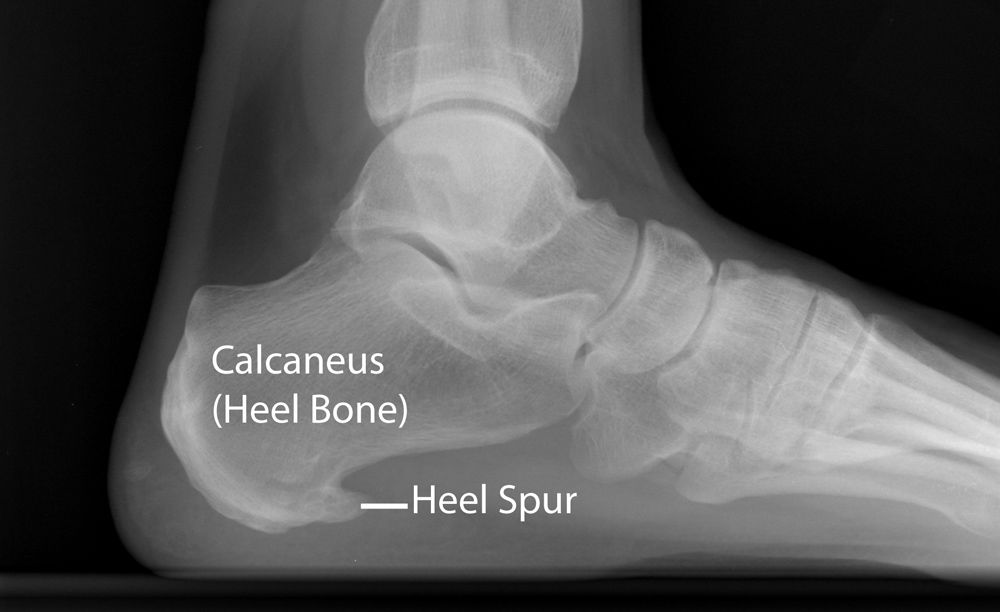

Will Shoe Inserts Help Plantar Fasciitis - Propét Ghillie Walker - Open Toe Casual Shoes | Flow Feet : We consulted physical therapists and podiatrists on the best shoes for plantar fasciitis, whether you're looking for sandals, running shoes, or slippers.. Get the latest news and events plantar fasciitis is a common condition that causes heel pain. Enter search terms and tap the search button. Plantar fasciitis occurs when the band of tissue in the arch of the foot becomes irritated causing heel pain. The best shoes for plantar fasciitis should be high quality, supportive, and comfortable. Plantar fasciitis is a painful inflammation of the plantar fascia, a fibrous band of tissue on the bottom of the foot that helps to support the arch.

Plantar fasciitis occurs when the band of tissue in the arch of the foot becomes irritated causing heel pain.

It can be caused by a number of factors and causes heel pain. This is a condition in which your plantar fascia, a ligament in your foot that connects your toes to your heel, tightens up. Plantar fasciitis is a pain disorder which affects the heel and the bottom of the foot and is the most common cause of foot pain. Leah groth is a freelance writer and editor with a focus in health, wellness, and lifestyle. The plantar fascia is tissue that runs along the bottom of your foot.